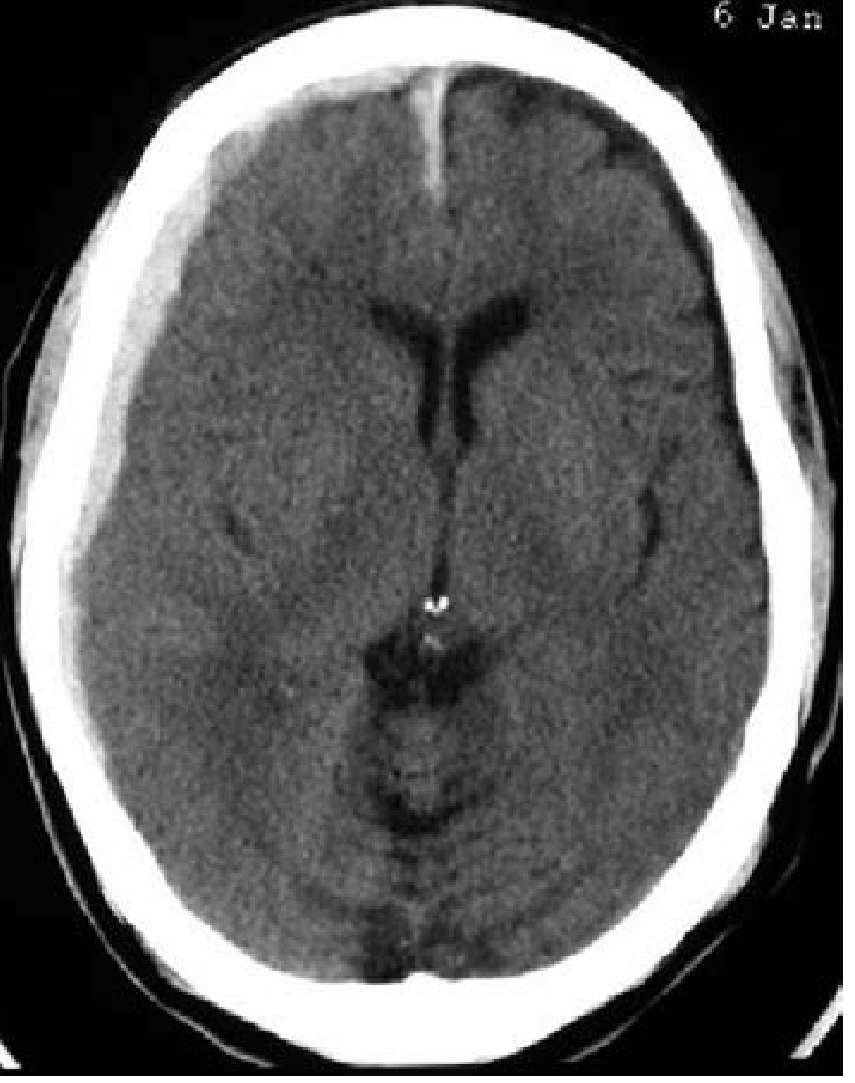

| Acute | Hyperdense (white), crescent-shaped, crosses suture lines |

| Subacute | Isodense — easily missed |

| Chronic | Hypodense (dark) — iron has been metabolized |